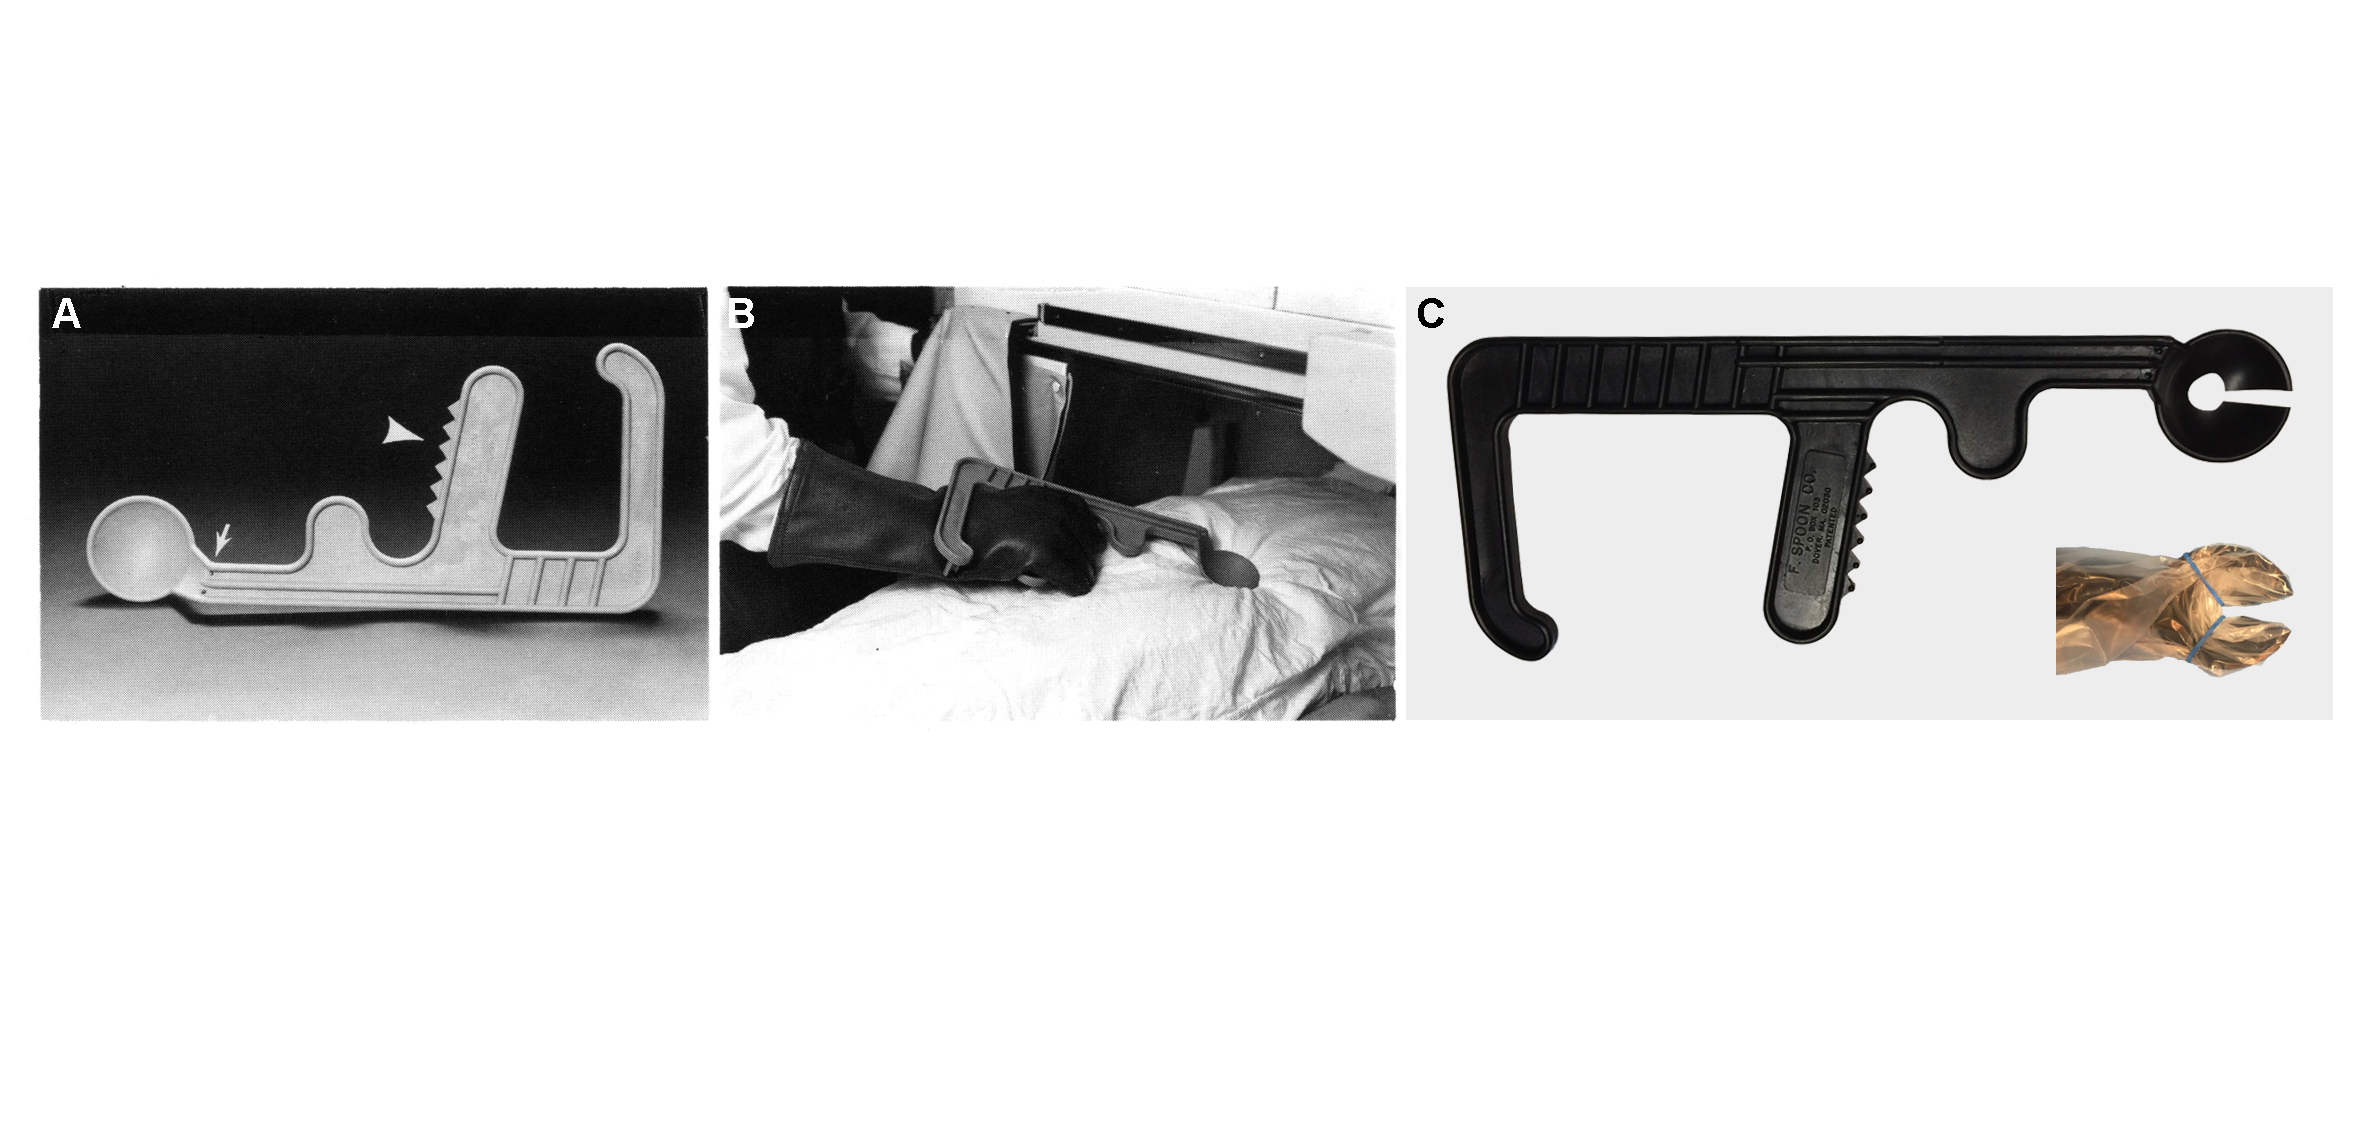

I am a computational designer, architect and geometry junkie - currently a research fellow at Harvard University’s Wyss Institute for Biologically Inspired Engineering studying geometry-function relationships in biological composites and fabricating their synthetic analogs through additive manufacturing. I also work at Brigham and Women’s hospital’s surgical planning lab

designing hardware for sizing heart valve prosthesis and image guided surgery. My interests include computational geometry, additive manufacturing and developing tools for the web.